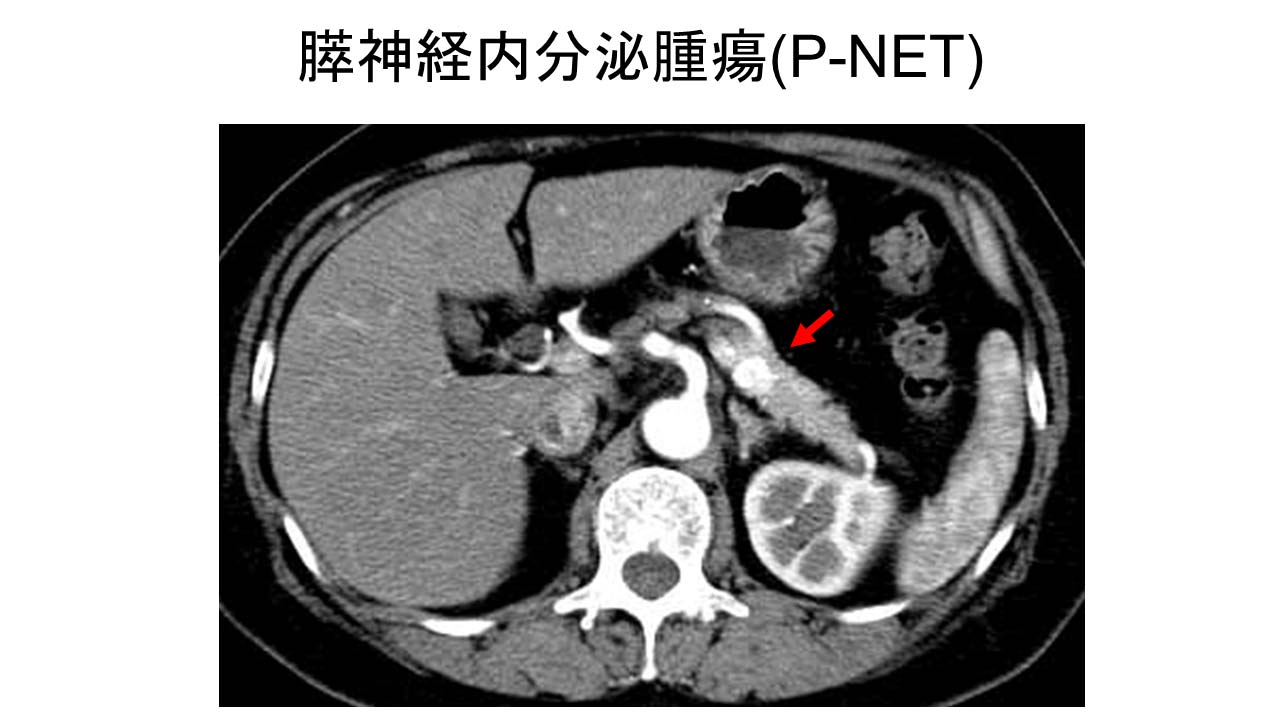

- 膵臓

- 膵臓および消化管腫瘍の治療:医師は、胃酸過多などの症状を管理するための薬を処方できます。また、外科的に腫瘍を切除したり、肝腫瘍を凍結または焼却したりすることもあります。非常にまれなケースですが、非癌性 MEN1 腫瘍であっても医師が化学療法を使用することがあります。